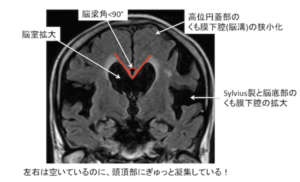

| 検査 | 【画像検査】 頭部CT・MRI:DESHが特徴(不均衡な所見を示す水頭症で、正常圧水頭症に特徴) ①脳室拡大:Evans index 0.3以上、冠状断像で脳梁角90°以上 ![]() ②シルビウス裂拡大 ③高位円蓋部および正中部の脳溝・くも膜下腔の狭小化 ![]() ④側脳室下角の拡大(ニコニコサイン) ![]() |